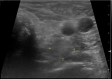

Figure 1

Figure 1. An ultrasound of the neck shows a solid area located lateral and inferior to the left thyroid gland.